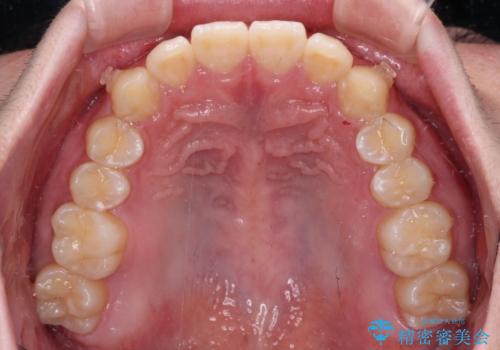

- 前方に傾斜した前歯を気にして来院された患者様です。

強く食いしばってしまう癖があり、下顎前歯に押し出されて上顎前歯が前方へ斜めに突き出している状態でした。

IPR(歯と歯の間を削る)を多用して、インビザラインにて矯正治療を行うこととしました。

口元を引っ込めるためのゴムかけを頑張っていただき、満足のいく上顎前歯の傾斜へ改善することができました。